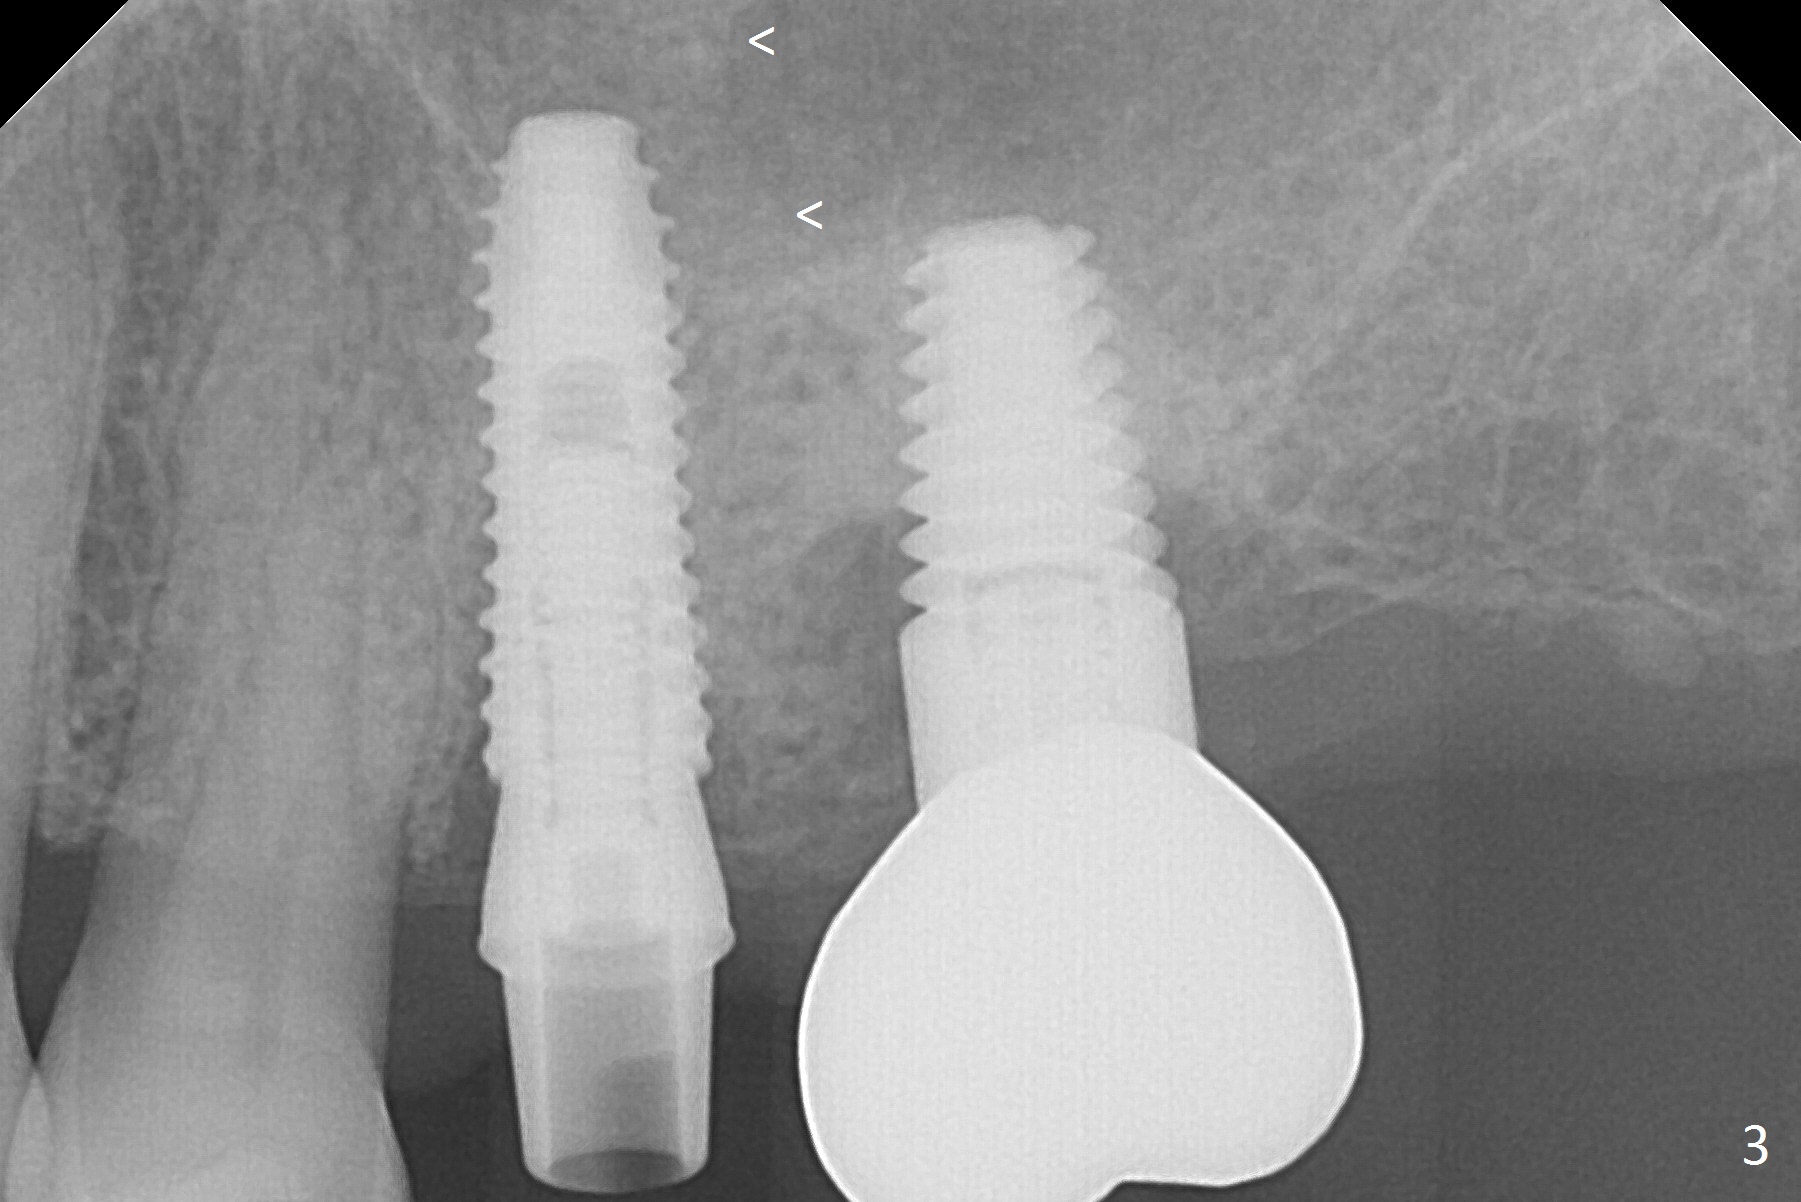

A Linderman bur is used to move the initial osteotomy distal. By the time of 3 mm in place, the trajectory seems to have improved; the sinus floor has been penetrated (Fig.2). Retrospectively, the parallel pin is not as sharp as the 2 mm drill to penetrate the perforated sinus floor (Fig.1).

After placement of allograft in the sinus (Fig.3 <), a 4x11.5 mm UF implant is placed with 45 Ncm. Following bone graft placement in the buccal gap, Osteogen tape lingually and insertion of a 4.5x4(3) mm abutment, an immediate provisional is fabricated.